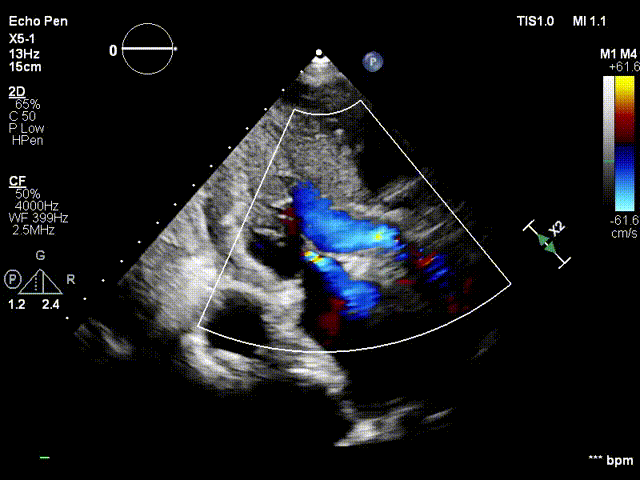

超声影像:

血流动力学改善,瓣膜形态良好,微量瓣周漏。